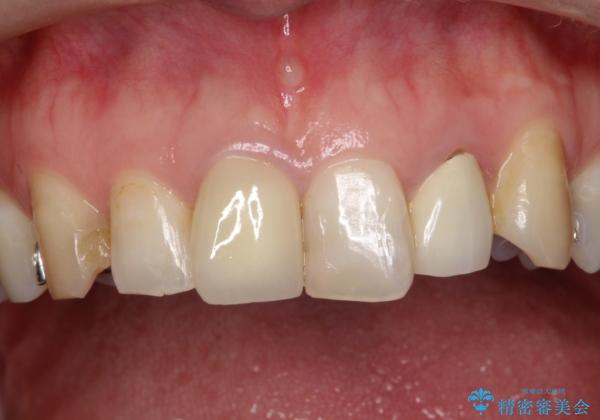

形態も色調もまわりの歯とは、調和がとれておらず、目立っていました。

今回治療することで、自然な前歯になったと喜んでいただけました。